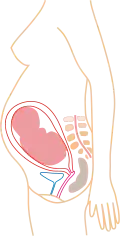

Stadia in beeld

- (aantal maanden refereert aan PML)

2 maanden 3 maanden

3 maanden 4 maanden